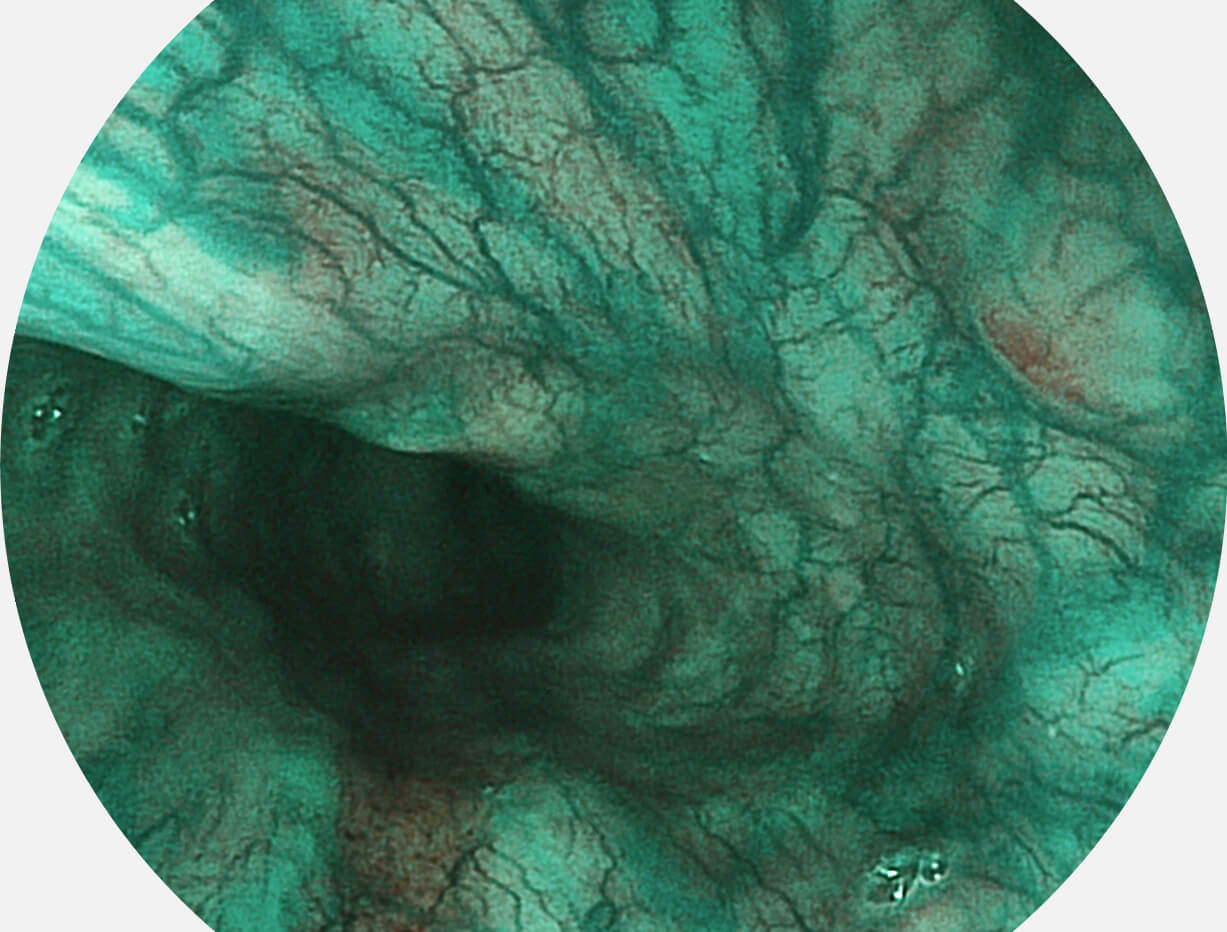

Versatile Intelligent Staining Technology, VIST

强调浅层黏膜结构的同时,保证照明亮度和提升浅层微血管与中层血管颜色对比度,病变边界更清晰。

VIST图像